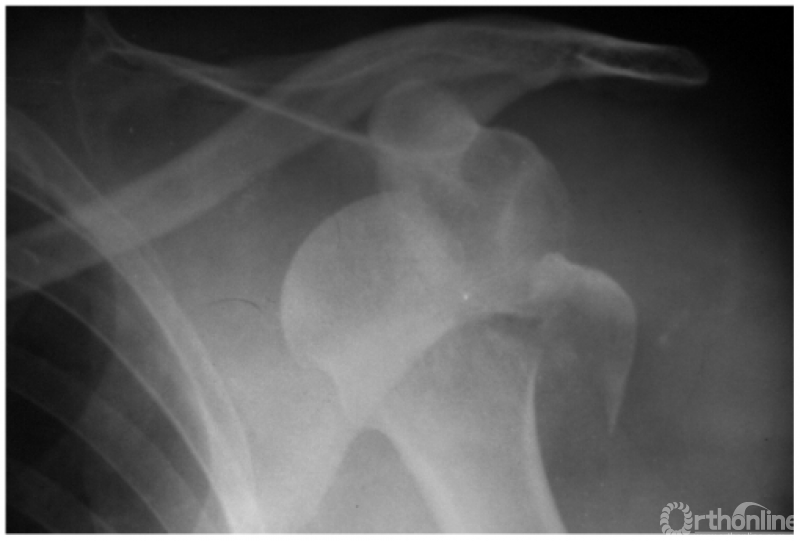

例2:希-萨(Hill-Sachs)二氏损伤。肱骨头后外侧劈裂骨折形成楔形缺损,骨折块下移并肩关节喙突下脱位(如下图)。